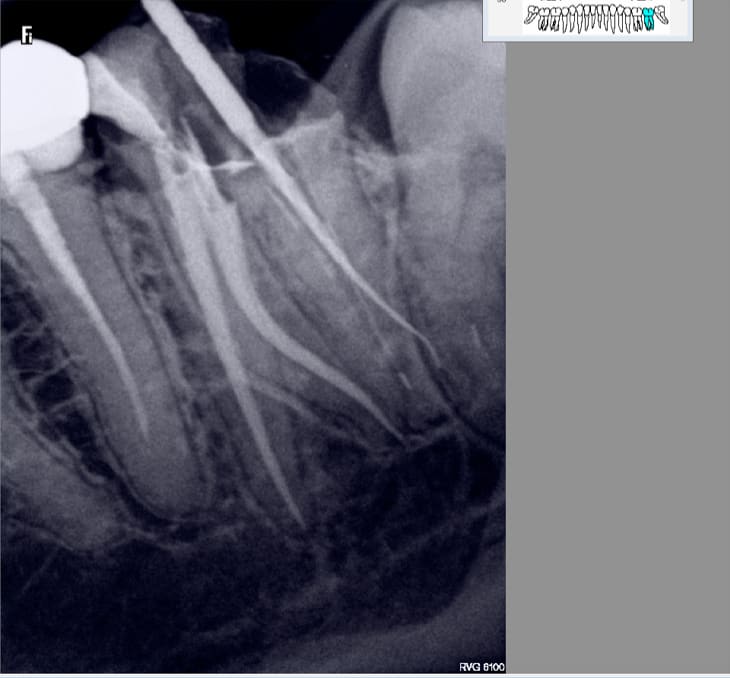

lachmar

02/02/2017 à 13h20

enlaye écrivait:

----------------

>

> ç est un Labrador qu'il te faut :-))))))))

on fait un deal ?

tu me montres 2 radios en incidence oblique de 2e MV obturés et je m'achète un lab )))

chicot29

02/02/2017 à 18h47

Et d'une. RTE s'il vous plait. -)